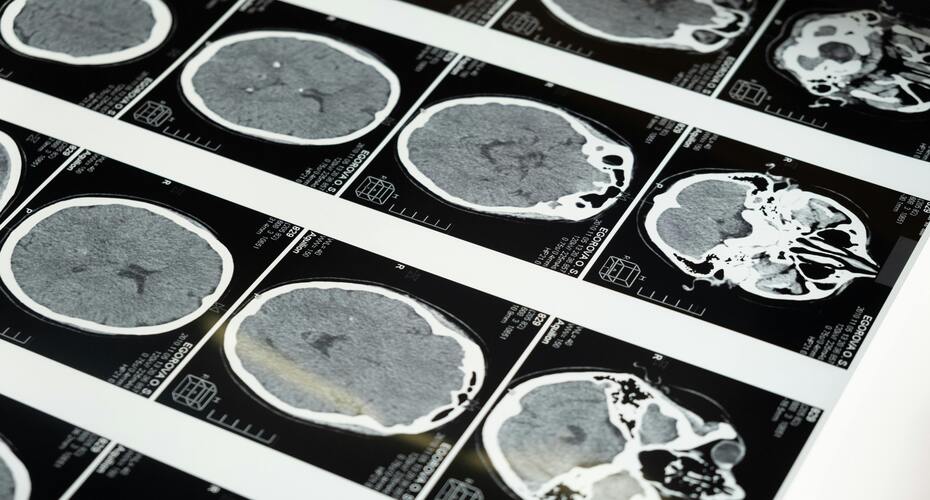

Clinical and Biomedical Sciences